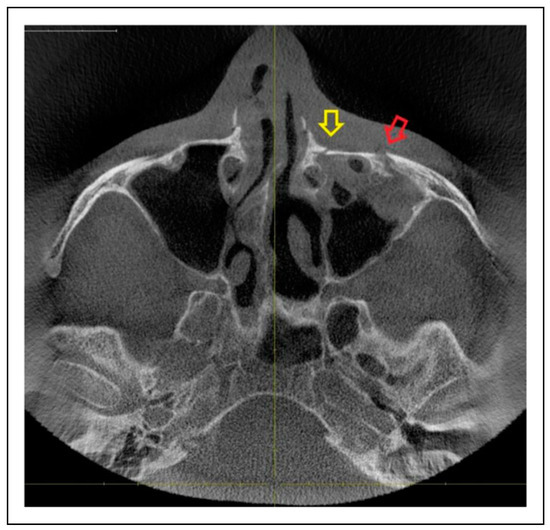

- Zygomaticosphenoidal suture (ZS)—the anterolateral orbital floor

- IOR + ZS suture

- IOR + ZF suture + ZS suture